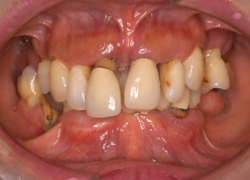

プラークコントロールの前後で、歯肉の変化を見てみましょう

約4ヶ月にわたるプラークコントロールのあとです。腫れていた歯肉は引き締まり、口臭も無くなりました。

もちろんこれだけで歯周病治療が終了するわけではありませんが、このようにご自身でプラークコントロールが上手くできるようになる事は全ての治療の基本となります。